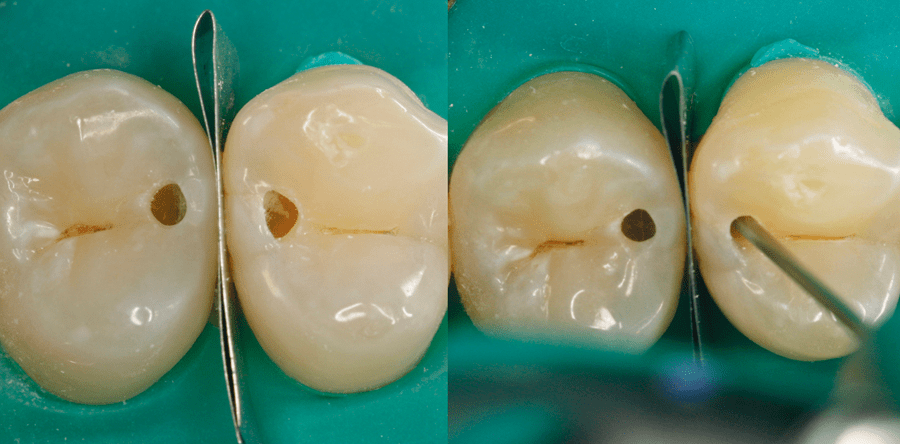

Der folgende Fall zeigt die typische Situation einer Zahnzwi- schenraumkaries, welche zwei Zähne eines Kontaktpunkt- bereiches betrifft. Bei intakten Okklusionsflächen schimmern bereits die Defekte dunkel aus der Tiefe der Prämolaren hervor (Abb. 1). Nach Kofferdamlegung werden mit einem Fissurendiamanten die ersten Sondierungsbohrungen durchgeführt (Abb. 2). Diese dürfen nicht zu nah an der approximalen Randleiste liegen, um deren Fraktur bei weiterem Vorgehen zu vermeiden. Die Bohrung soll einen ersten Eindruck zur Lage und Ausdehnung der Karies ermöglichen. Vor Exkavation wird der Approximalraum durch ein gefaltetes Stahlmatrizenband separiert (Abb. 3). Ich beginne dann stets mit kleinen Rosenbohrern, und wähle entsprechend der Defektgröße anschließend größere. Je nach Erfordernis muss parallel die Bohrung mittels Diamantschleifer erweitert werden.